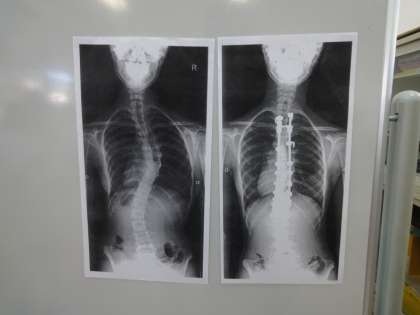

6年生は保健室で体重測定をするとともに,姿勢良く過ごすことの大切さを学びました。自分の姿勢について見つめ直すとともに,「体を大切にしていきたいな。」と考えていました。